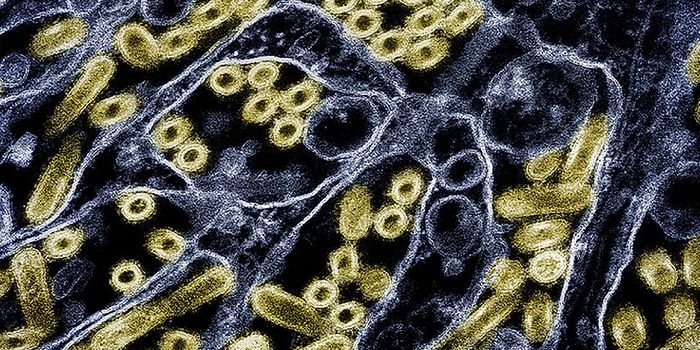

SEP 05, 2024Cell & Molecular BiologyCorynebacterium matruchotii ia a common bacterium that lives in human dental plaque; a colony is seen in this image by S ...